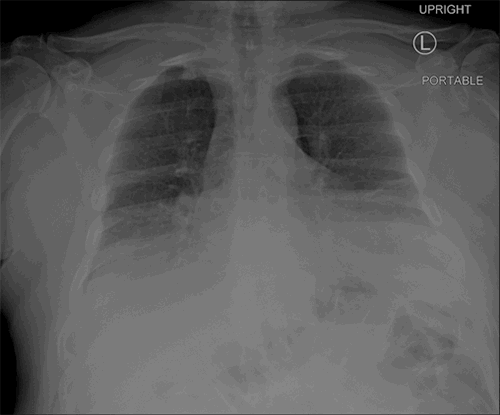

The postoperative course was relatively uncomplicated, and the patient was extubated on the third postoperative day after initially failing two spontaneous breathing trials. He was continued on nebulizer treatments and antibiotics. No specific antitussive medication was administered. A postoperative chest radiograph is shown in Figure 3. A chest CT performed two years postoperatively showed an intact repair (Figure 4).

Figure 3. Plain radiography of the chest immediately following diaphragm repair